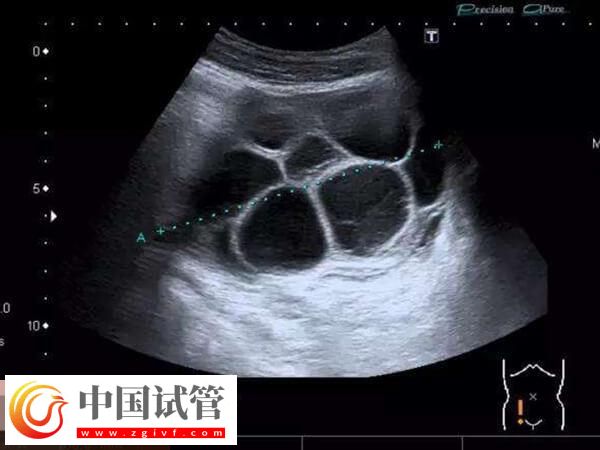

取卵后卵巢过度刺激综合征,这也是导致女性在移植术后腹水的重要原因,这种病症主要是有对于促排卵药物的剂量使用把握不准,或者女性的体质较为敏感,对于卵巢刺激过度,从而诱发卵巢刺激综合征,进而导致腹水。

试管婴儿胚胎移植后腹水的原因一般有多卵泡同时发育,这种渗出会导致血液浓缩和有效血容量减少,严重时可能威胁到生命安全。对此建议患者要注意及时就医质量。